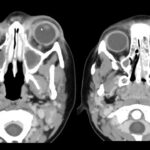

Dados da Secretaria de Saúde de São José do Rio Preto apontam que no município são feitas em média três mil 500 consultas oftalmológicas por mês. A medicina está a favor das pessoas. Tratamento e equipamentos de última geração que possibilitam o diagnóstico precoce e permitem ao médico cada vez mais dizer ao paciente que ele está curado. O tratamento é basicamente clínico. Quando o paciente chega no seu consultório, você vê ele com uma própria vermelha, dolorosa, quente. Aqui, você vê que tem que acionar explosivos que a gente chama de infecção. Alguma coisa está errada ali naquela região, aí então você vai fazer os exames complementares como a tomografia de órbita que aí sim, se for uma patologia de órbita, um abscesso periorbitário, que é mais comum principalmente em crianças, você detecta já no exame. Entre o hemograma, que também vai te mostrar um quadro infeccioso do paciente, que é onde você vai introduzir o tratamento medicamentoso, que antibiótico é o principal. É a causa mais comum da celulite orbitária é a meningite.